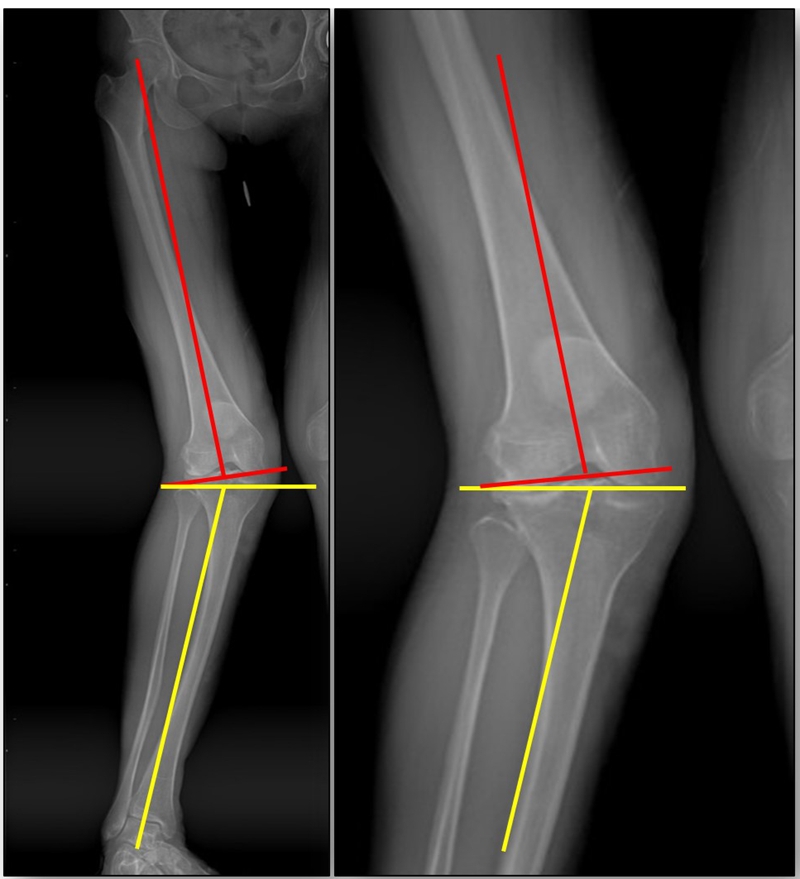

患者二,女性,膝外翻,膝外侧疼痛。通过做畸形分析后发现,该患者同时存在股骨侧畸形、胫骨侧畸形和关节内畸形(LDFA=82°,MPTA=104°,JLCA=6°)。

对于这类病人如何进行术前设计的关键点就在于目标力线应如何设计。要在骨性截骨的时候纠正骨性畸形,关节内畸形要通过关节内的方法解决。因为JLCA不平行,所以要同时画股骨侧关节线和胫骨侧关节线,并垂直于股骨侧关节线做出股骨侧目标力线,垂直于胫骨侧关节线做出胫骨侧目标力线。

根据各自目标力线,分别计算股骨内侧闭合和胫骨内侧闭合角度。

此患者股骨内侧闭合6°,经股内侧闭合13°。